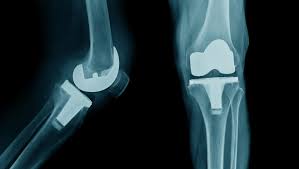

Low-cost joint replacement procedures at Varunam Super Speciality Hospital address a wide range of joint conditions, including:

These procedures aim to reduce pain, restore joint function, and improve long-term mobility. Therefore, patients regain the ability to perform daily activities comfortably and confidently after recovery.